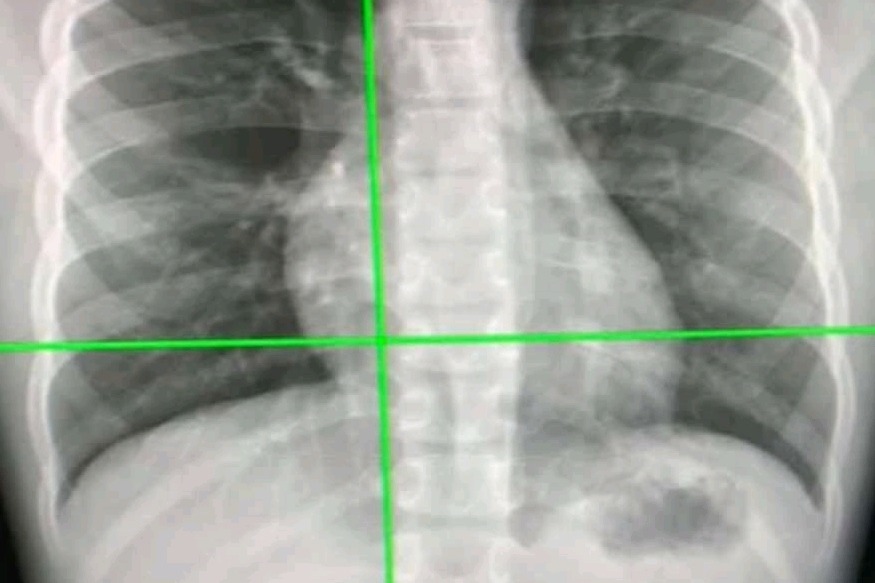

New AI tool can detect Covid infection from chest X-rays 98% accuracy

Sydney, Jan 9: Australian researchers have developed an artificial intelligence (AI) system that can rapidly detect Covid-19 from chest X-rays with more than 98 per cent accuracy, and may be more beneficial than the currently used RT-PCR test.

The new AI system, detailed in a paper published in the journal Scientific Reports, uses a deep learning-based algorithm called a Custom Convolutional Neural Network (Custom-CNN) that is able to quickly and accurately distinguish between Covid-19 cases, normal cases, and pneumonia in X-ray images.